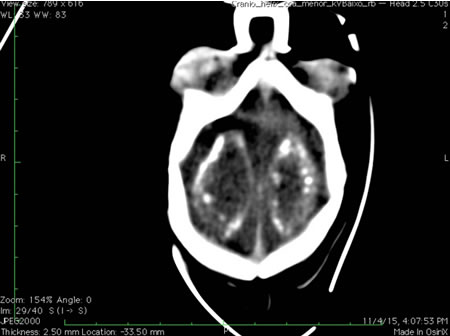

CT/MRI head (newborn)

Test

Recommended in infants with microcephaly (or craniofacial disproportion) where Zika infection is suspected in the mother during pregnancy, or if any neurological signs/symptoms are present in the infant.[178]

Either CT or MRI can be performed; however, an MRI may provide more detail and can potentially detect other conditions.[178]

The most common feature found on CT is brain calcifications in the junction between the cortical and subcortical white matter, often with a simplified gyral pattern and predominance of pachygyria or polymicrogyria in the frontal lobes. These calcifications often resolve; therefore, the absence of calcifications should not exclude the diagnosis, and the presence of calcifications should not be consIdered a major criterion for diagnosis.[179]

Other findings include abnormalities of the corpus callosum (hypogenesis or hypoplasia), enlarged cisterna magna, ventriculomegaly, delayed myelination, and hypoplasia of the cerebellum and brainstem.[180][181]

Although the risk appears to be greatest with infection in the first or second trimester, signs of congenital brain injury (e.g., subependymal cysts, lenticulostriate vasculopathy) due to Zika virus infection acquired during the third trimester of pregnancy have been reported.[158]

[Figure caption and citation for the preceding image starts]: CT scan of the head of an infant with Zika virus infection showing a clear distribution of periventricular calcificationsFrom the personal collection of Dr Geraldo Furtado, MD, MSc (used with permission) [Citation ends].

may show intracranial calcifications, ventriculomegaly, cerebellar hypoplasia, callosal abnormalities, or ocular findings